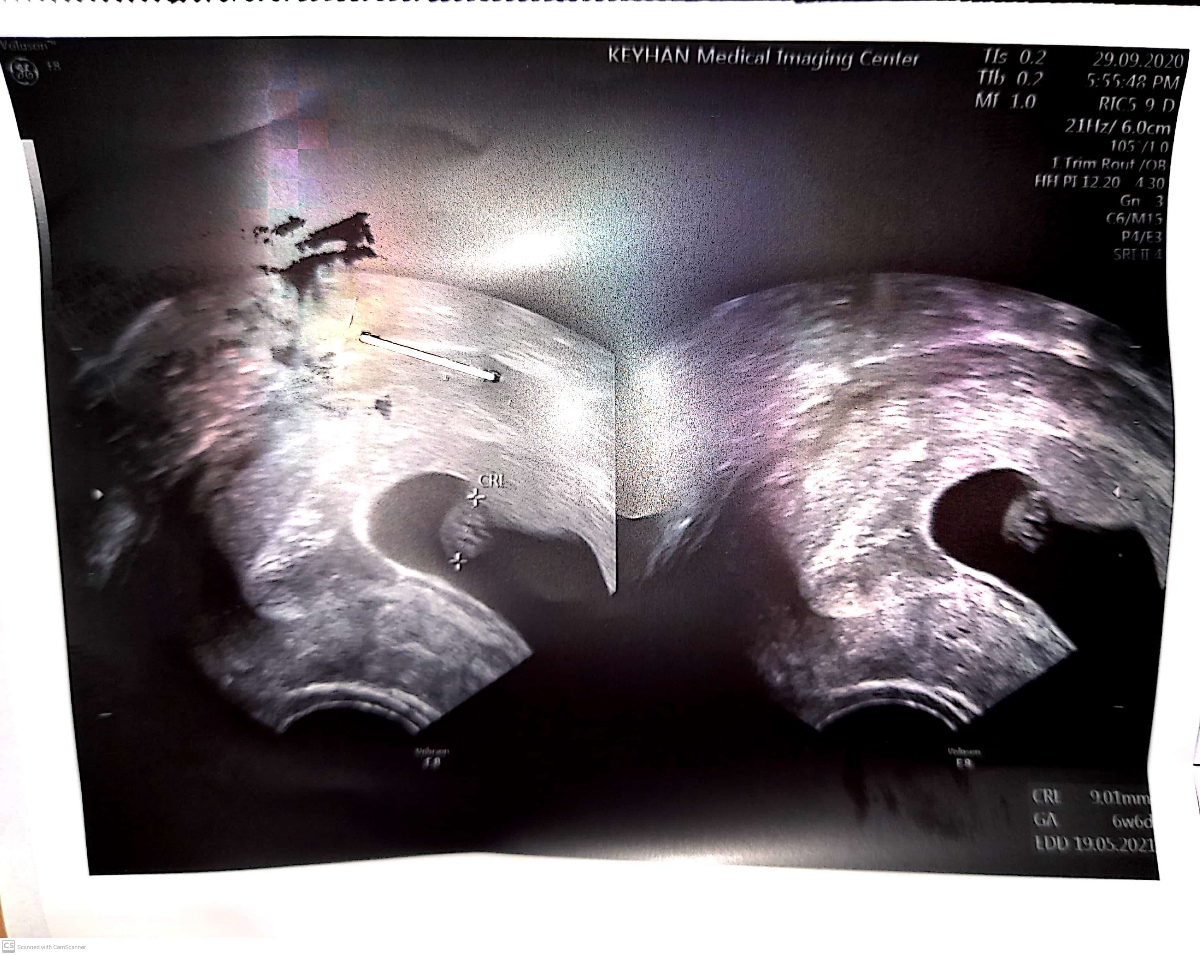

جان دلم در سونوگرافی شما جنین و ضربان قلب رویت شده است و اختلاف حدوداً یک هفته میان سن حاملگی بر اساس طول جنین و سن حاملگی بر اساس اولین روز آخرین قاعدگی مشکلی نداشته و اهمیتی ندارد اما اگر آزمایشات ابتدایی بارداری را انجام نداده اید حتماً در این ویزیت درخواست شوند تا روال بارداری به بهترین شکل ممکن پیش برود. تنها نکته حائز اهمیت در سونوگرافی شما دیده شدن ۳ تا ۴ میوم در رحم بوده که از نوع ساب سروزال هستند. این دسته از میوم ها در دیواره خارجی رحم رشد کرده و مشکلی را برای بارداری و جنین ایجاد نمیکنند. در واقع صرفاً باید در سونوگرافی ها به طور پیوسته بر روی آنها نظارت داشت تا مطمئن شویم که بیش از حد بزرگ نمی شوند🌹🌹🌹

طبق تقویم اوما و تاریخ پریودم من توی ۶ هفته و هفت روز رفتم سونو و سونوگرافی سن بارداری رو ۶ هفته و ۶ روز تشخیص داد

عزیزم پس اختلافی وجود ندارد، چون تاریخ انجام سونوگرافی را نگفته بودید فکر کردم به تازگی در هفته 8 که در تاریخچه اوما نوشته شده است سونوگرافی را انجام داده اید💗